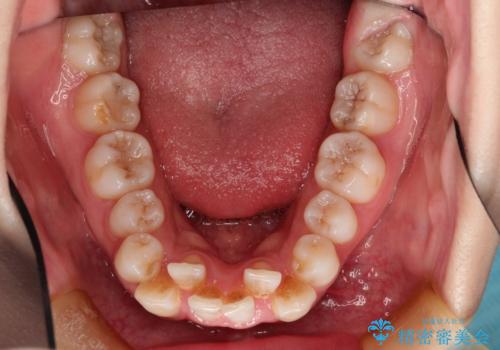

- 前歯のデコボコと上顎の前突感による口の閉じにくさを気にして来院された患者様です。

目立たない装置を希望されたので、上顎が裏側装置のハーフリンガルを選択し、上下左右の小臼歯(計4歯)を抜歯して矯正治療を行うこととしました。